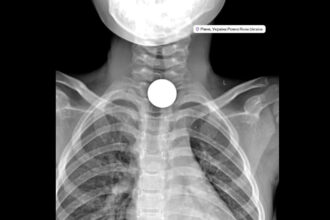

У Рівному дитячий хірург Максим Красько успішно видалив монету, яка застрягла у…